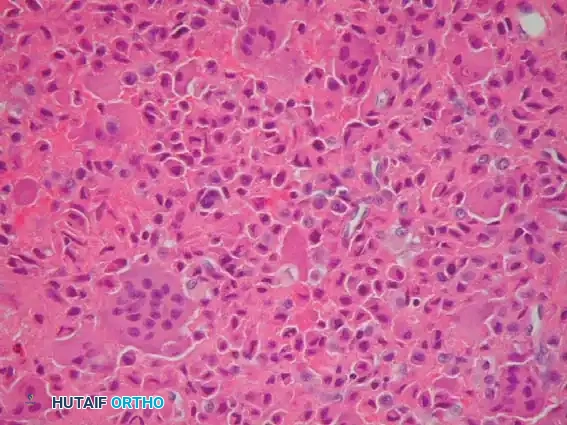

Fig. 21-4F: Typical microscopic appearance of chondroblastoma, characterized by mononuclear chondroblasts and scattered osteoclast-like giant cells.